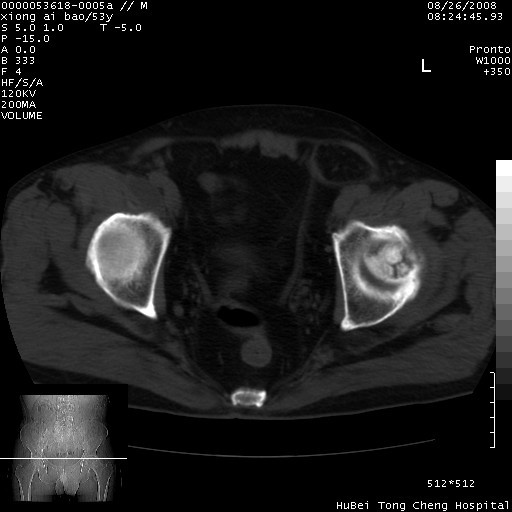

标题: CT15583:M,53Y。请老师指教分析骨盆及其他病变。 [打印本页]

标题: CT15583:M,53Y。请老师指教分析骨盆及其他病变。

双侧股骨头无菌坏死,左侧腹股沟斜疝。

非常典型病例,双侧股骨头坏死伴双髋关节周围软组织肿胀,左腹股沟疝。

支持双侧股骨头无菌坏死,左侧腹股沟斜疝。

双侧股骨头坏死伴双髋关节周围软组织肿胀,左腹股沟疝。

双侧骨股头无菌性坏死,左侧腹股沟疝

双侧髋关节肿胀明显,感觉还不能排除结核。

考虑双侧髋关节结核,左侧腹股沟疝